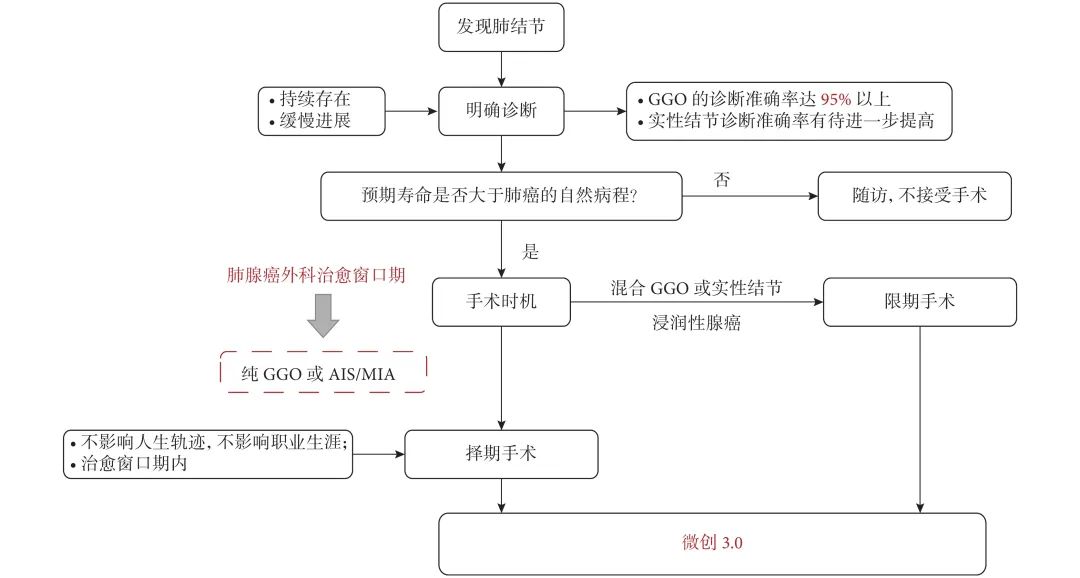

没想到我这么大岁数,切掉一个肺叶的十年后,再次做这么复杂的手术还这么顺利。 D大爷今年72岁,10年前曾行左肺上叶切除+淋巴结清扫术,手术标本病理为腺癌,术后给予了四次化疗。当时的胸部CT即可见右肺上叶小结节影,术后定期复查,病灶缓慢增大,一度略有缩小,此后再次逐渐增大。结合患者一直随访的影像学资料,杨如松院长考虑为右上肺新发恶性肿瘤。 2015年胸部CT 2020年胸部CT 虽然患者及其家属手术的意愿非常强烈,但此手术难度较高,原因在于: 1.患者年龄较高,手术风险大。 2.患者10 年前肺癌手术切除左边肺的一半,肺功能丧失较多。 3.病灶在右上肺的深部,切除有一定的难度。 为了保证患者术后的生活质量,我们不能够做肺的楔形切除这样的简单肺手术,而需要行肺段的切除。 EDDA重建提示病灶位置深 如果放在以前该患者就只能做做放化疗等保守治疗了。幸亏南京胸科医院目前引进了各种国内乃至国际上的先进技术。 如EDDA术前三D成像技术;只有单一3cm长切口的单孔胸腔镜技术;近红外荧光镜肺段、亚肺段精准定位技术等。 有了这些技术,杨如松院长心中有了底气。杨院长根据病人的情况设计手术方案,尽量减轻手术创伤,让接受第二次肺部复杂手术的高龄病人能够耐受,并且在术后能够顺利恢复。 根据术前EDDA三维重建,患者进行了单孔荧光胸腔镜S1a+2a切除术,术中先用ICG反染法确定段间面,再用膨胀萎陷法印证段间面,这保证了手术切除的精准性。 患者术中快速病理为贴壁型腺癌,这也印证了杨如松院长术前对患者肺结节良恶性的判断。 术后5天,D大爷非常顺利的出院了。出院前开心的窦大爷连声感谢杨如松院长:没想到我这么大岁数,切掉一个肺叶的十年后,再次做这么复杂的手术还这么顺利,谢谢、谢谢! 基本情况